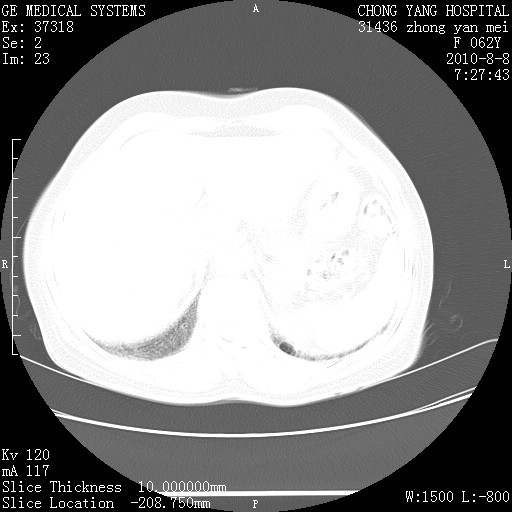

标题: CT28269:F62Y咳嗽胸痛数月。 [打印本页]

标题: CT28269:F62Y咳嗽胸痛数月。

两肺弥漫性间质纤维化伴继发性支扩。

双肺间质纤维化合并感染、肺气肿

两肺间质纤维化并牵拉性细支气管扩张。

考虑两肺间质性肺炎并肺间质纤维化,肺气囊形成。